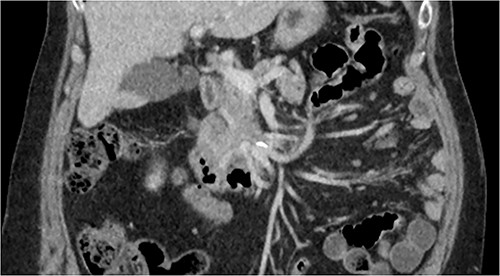

A multiphase CT of the pancreas had unexpected findings. There were no pancreatic masses on the arterial and portal phase study, and no paraaortic or mesenteric lymphadenopathy. The abnormal calcification seen on the previous study corresponded to a dilated vessel along the superior margin of the pancreatic body. This dilated vessel was an abnormal communication between a tortuous ecstatic gastroduodenal artery and the first branch of the SMA, a Buhler’s arc communication. The celiac axis origin was narrowed >90%. No other suspicious solid organ mass lesion was identified. Soft tissues were unremarkable (Figs 5–8).

Multiphase CT pancreas, axial view demonstrating abnormal communication between the CA and the SMA.

Multiphase CT pancreas, coronal view: the gastroduodenal artery, off the common hepatic, communicating with the first branch of the SMA.